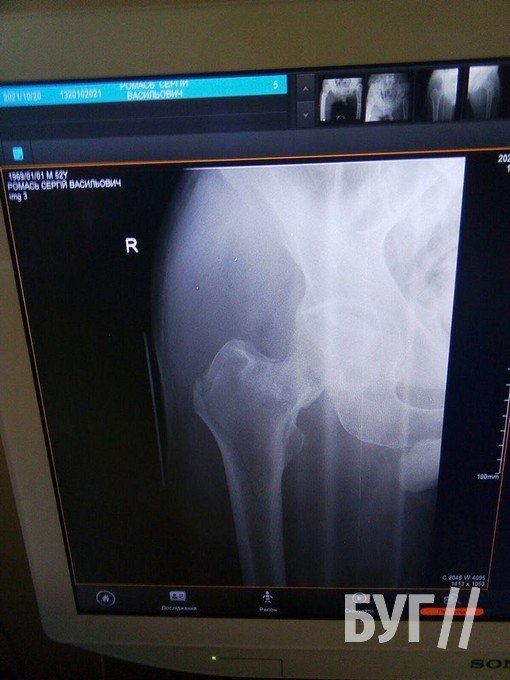

20 жовтня колишній шахтар Сергій Ромась отримав травму та потребує заміни суглоба і проведення операції на двох кінцівках.

У 52-річного чоловіка, який проживає у селі Суходоли, два переломи стегнових кісток і розтрощений кульшовий суглоб.